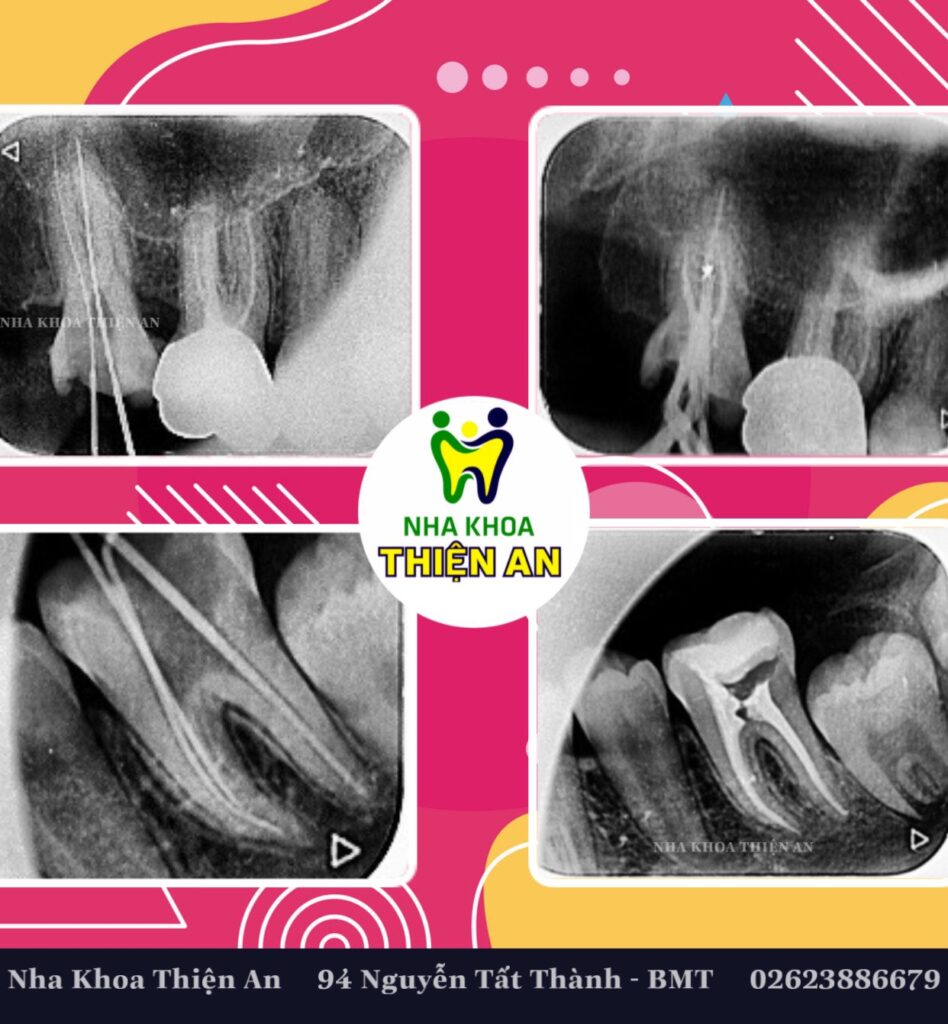

Điều trị tủy bằng máy nội nha tại nha khoa Thiện An BMT – Đăk Lăk giúp lấy sạch phần tủy hỏng tốt hơn, rút ngắn thời gian điều trị, xử lý được ống tủy cong….. giúp cho việc thành công sau điều trị tủy

Root canal treatment with an endodontic machine at Thien An BMT Dental Clinic – Dak Lak helps clean out damaged pulp better, shortens treatment time, handles curved root canals…. helping to achieve success after treatment. Root canal treatment

tại nha khoa Thiện An BMT – Đăk Lăk, 94 Nguyễn Tất Thành (đối diện Bitis)

- BS. CK2 Huỳnh Thanh Trung– Giám đốc Nha Khoa Thiện An, Nguyên Trưởng Khoa Răng Hàm Mặt, BVĐK Vùng Tây Nguyên

- ThS.Bs Nguyễn Thị Bích Ngọc, Nguyên Giảng viên Khoa Y Dược, Trường Đại Học Tây Nguyên trực tiếp điều trị.

at Thien An Dental Clinic BMT – Dak Lak, 94 Nguyen Tat Thanh (opposite Bitis)

- BS. CK2 Huynh Thanh Trung- Director of Thien An Dental Clinic, Former Head of Odonto-Stomatology Department, Central Highlands General Hospital

- Mrs.Dr Nguyen Thi Bich Ngoc, Former Lecturer of Faculty of Medicine and Pharmacy, Central Highlands University directly treated.